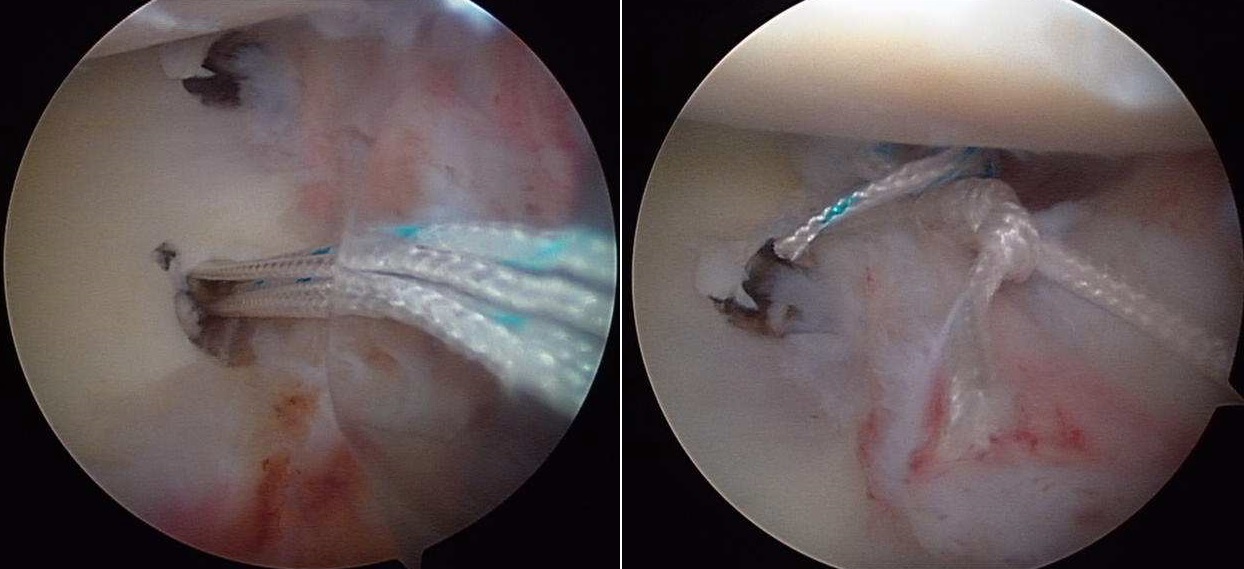

Fortunatamente non tutte le lussazioni richiedono un intervento chirurgico per il recupero completo delle attività del paziente. Il trattamento di prima scelta dopo il primo episodio di lussazione è quello conservativo: riduzione, applicazione di bendaggio e, dopo un periodo di immobilizzazione di alcune settimane, si inizia una progressiva attività di mobilizzazione e rinforzo muscolare, anche utilizzando elastici. Se l’instabilità persistesse e si ripresentassero lussazioni è indicato pensare alla risoluzione chirurgica. L’evoluzione delle tecniche operatorie dell’instabilità di spalla negli ultimi 20 anni ha permesso di rendere sempre più preciso l’intervento e soprattutto di personalizzarlo per le lesioni specifiche e per i singoli pazienti. La decisione su quando eseguire un intervento di riparazione delle lesioni e di rinforzo capsulare (capsuloplastica) viene presa in accordo con il chirurgo. Tuttavia lo stesso paziente avverte a un certo momento la necessità di correggere la situazione per il disagio non più tollerabile nella vita lavorativa e di relazione.

Nella scelta della tecnica di intervento influiscono diversi elementi: età, numero di lussazioni o, in assenza di queste, durata del dolore alla spalla e grado di impedimento durante l’attività sportiva o lavorativa, struttura muscolare, livello di carico durante il lavoro, pratica di sport o attività motorie a livello agonistico o amatoriale. Fondamentale è anche poter escludere la presenza di fratture associate alla lussazione e per questo un esame più approfondito con TAC o RMN può essere di grande utilità.

Questa tecnica non è raccomandabile in caso di fratture associate o di insufficiente resistenza del tessuto capsulare. In queste condizioni la tecnica artroscopica può avere una elevata incidenza di recidive di lussazione. La procedura tradizionale “aperta”, indicata in pazienti che presentano facili lussazioni, prevede invece l’incisione chirurgica di 6-8 cm sulla porzione anteriore della spalla e l’utilizzo di varie tecniche di plastica capsulare che conferiscono la corretta tensione. Tra queste è molto utilizzata la metodica di Latarjet (Fig. 4) che prevede il trasferimento della coracoide sul bordo anteriore della glena, fissata con viti, particolarmente indicata se vi è una lesione della struttura ossea della glena.